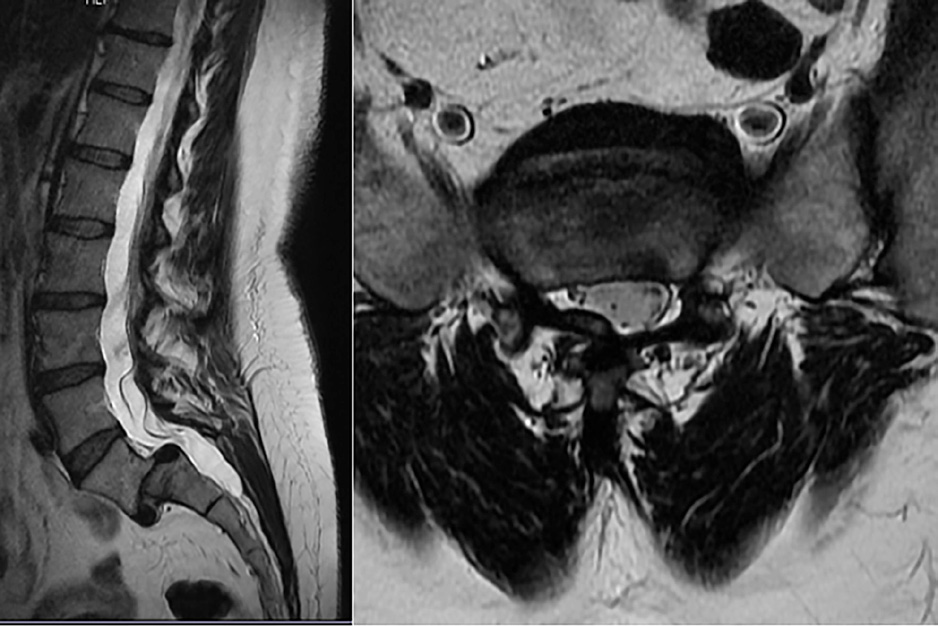

- RMN de columna lumbar: espondilolisis bilateral L5 con espondilolistesis grado II sobre S1. La listesis condiciona discreta estenosis de canal a nivel sacro.

- Radiografías simples columna lumbosacra: espondilolistesis L5-S1 grado II-III.